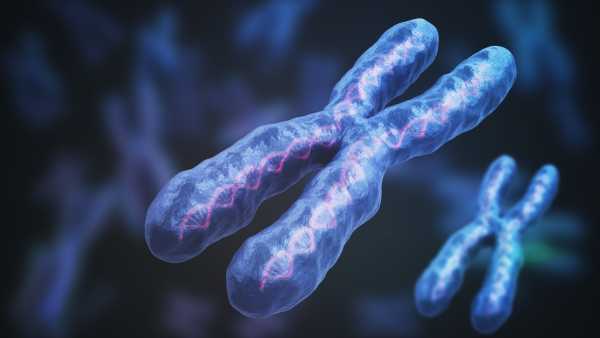

Жінки в 4 рази частіше хворіють на аутоімунні захворювання, ніж чоловіки. Можливо, причиною є Х-хромосома.